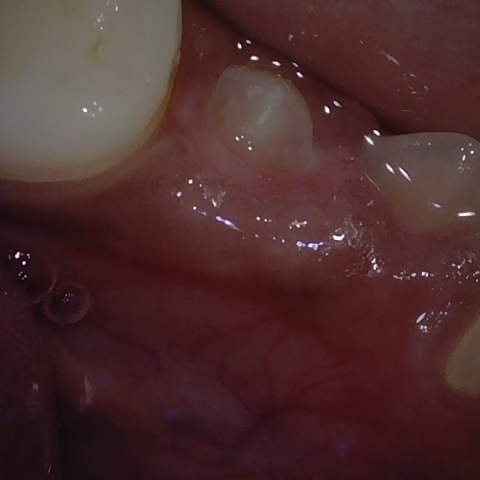

NHD25470

Annotated as "Good"